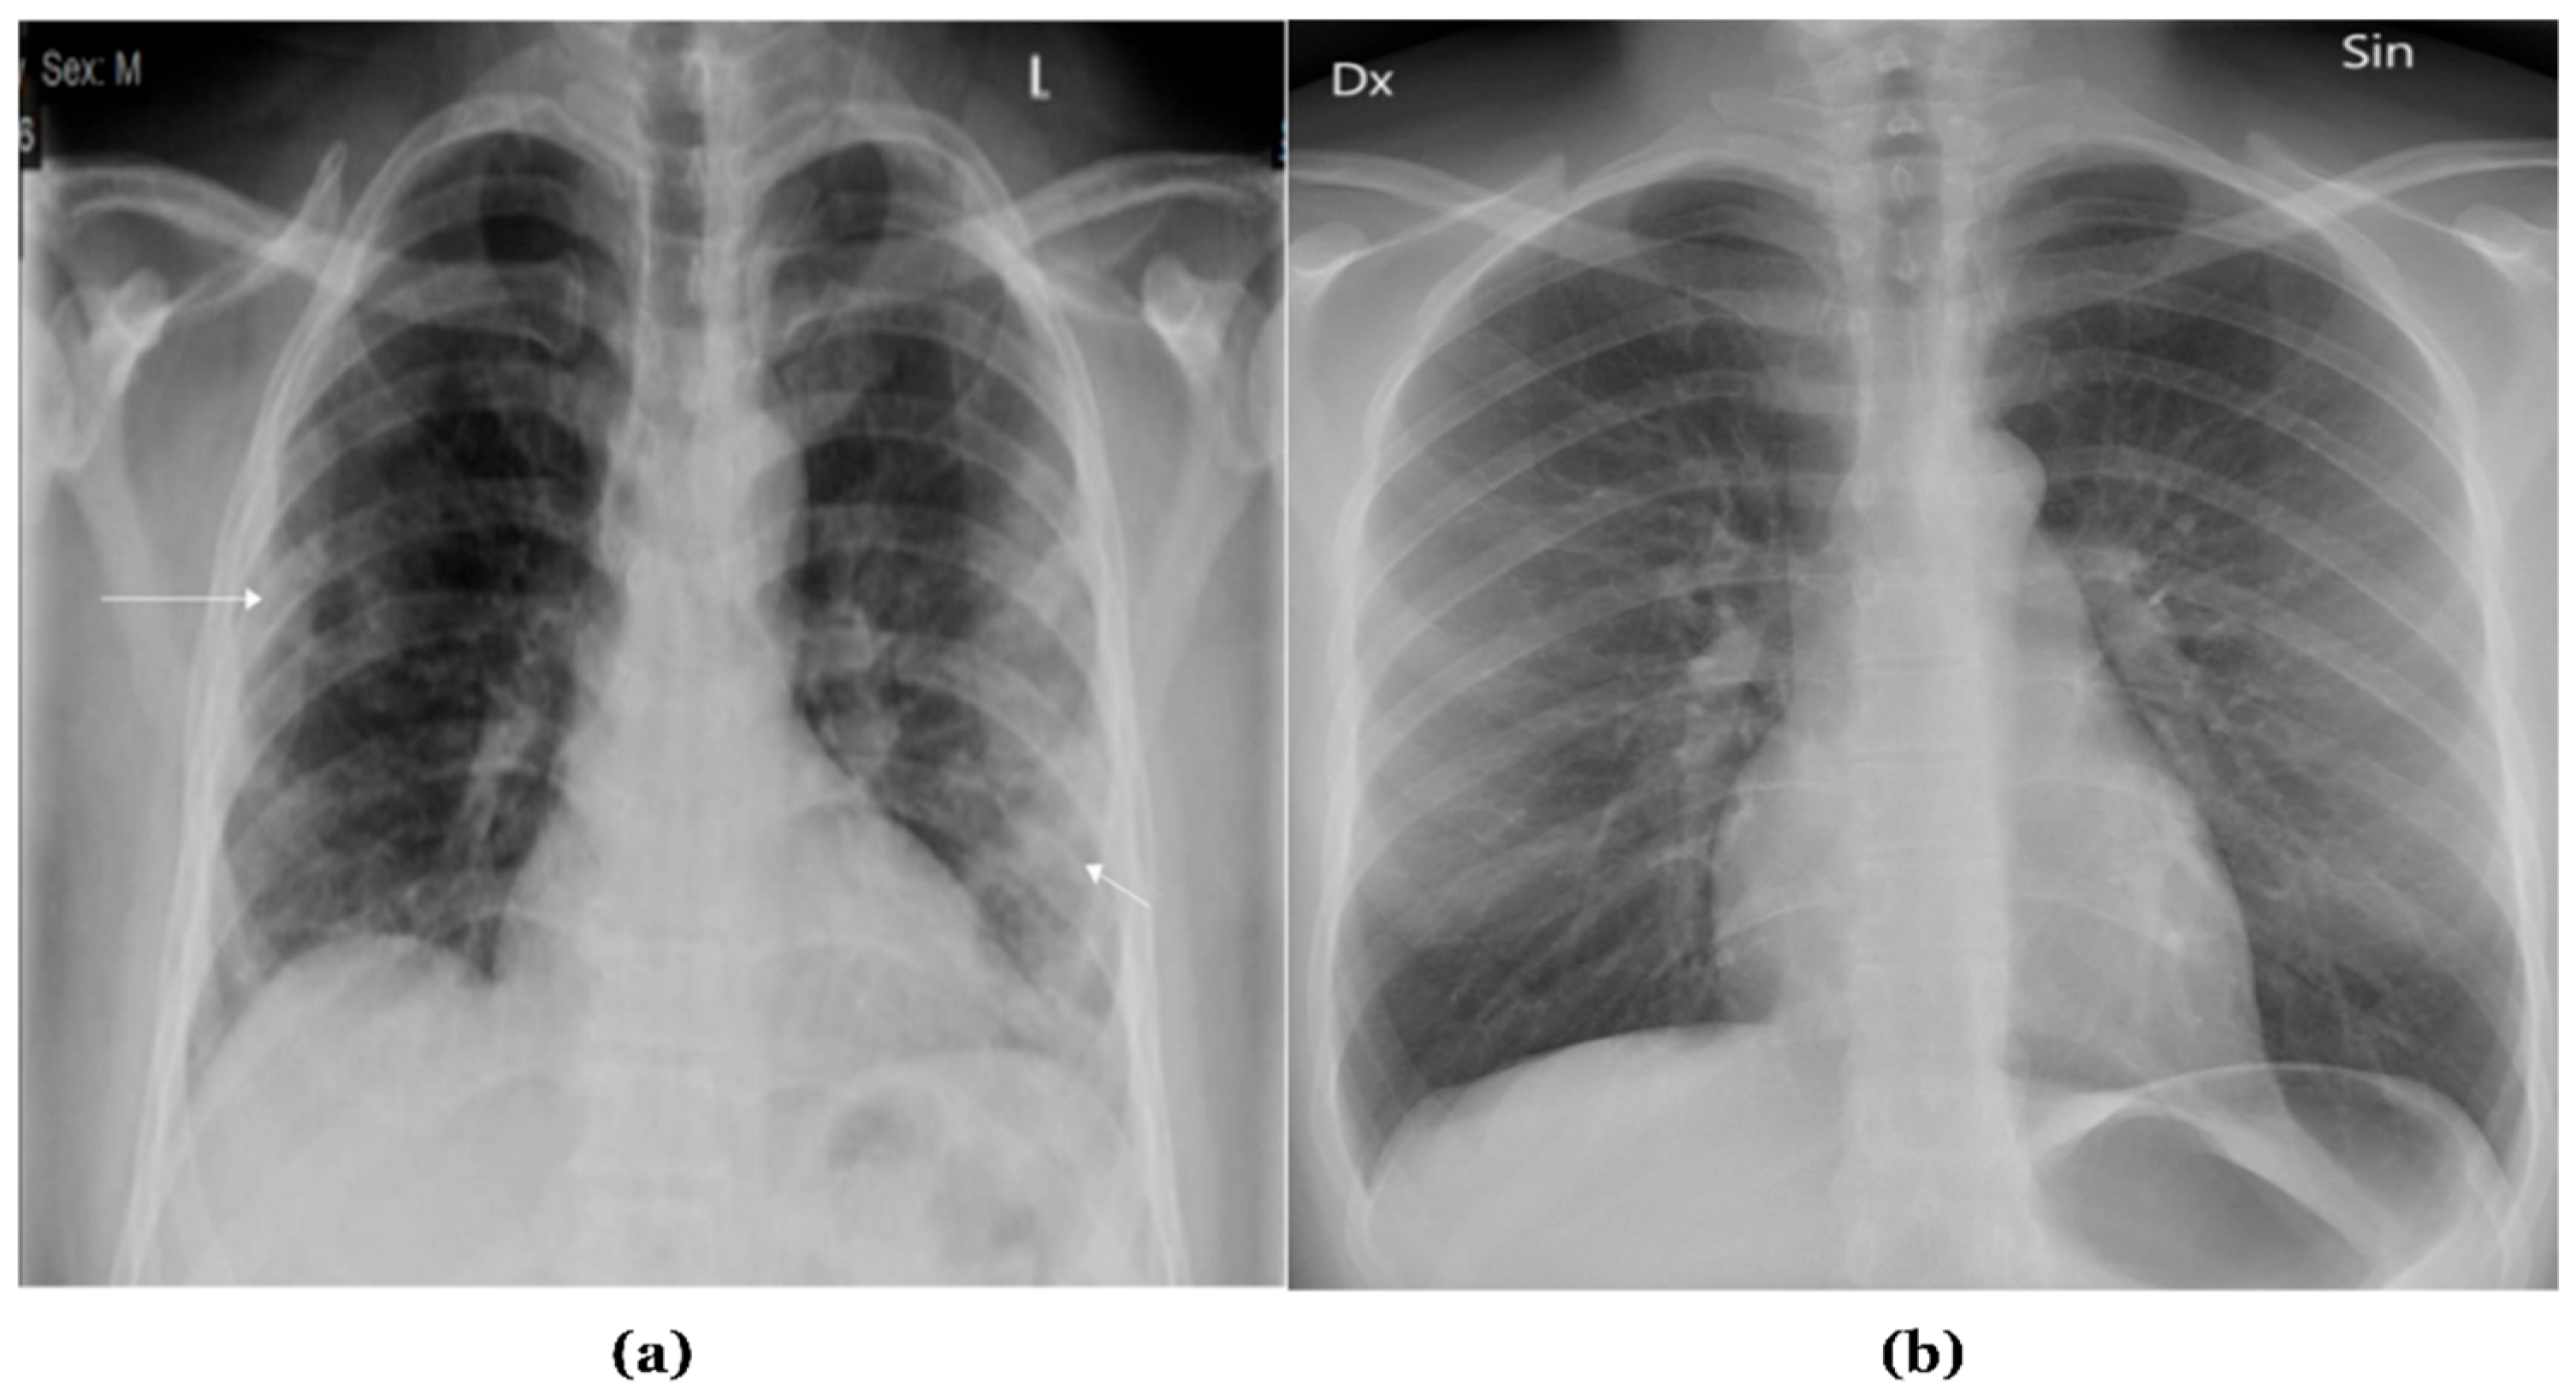

X-ray radiographies provide a cost-effective and non-invasive method for evaluating various body organs [1]. X-rays are recognized as an effective diagnostic technology for many illnesses and abnormalities, and they can also be employed to monitor conditions throughout treatment. Approximately 3.6 billion X-ray images are taken worldwide each year [2]. This includes about 150 million chest X-ray radiographs (CXRs) performed alone in the United States. CXRs are grey-scale images produced by directing X-rays at an individual’s body while it is positioned against a metallic surface. Figure 1 presents samples of chest X-ray images.

Figure 1.

Samples of Chest X-ray images: (a) Abnormal; (b) Normal.